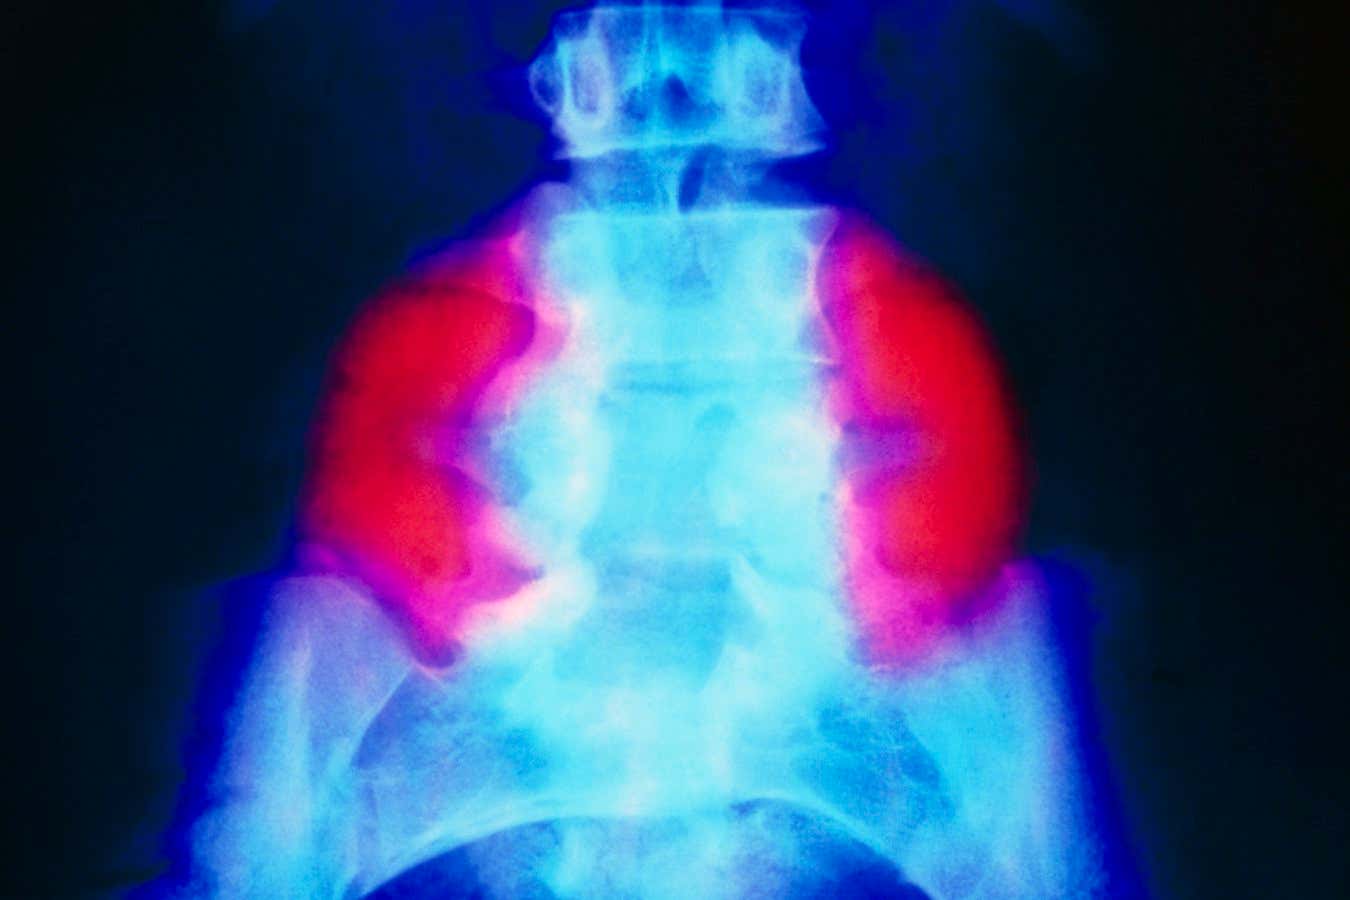

A false-colour X-ray showing a large neural tube defect (red) on both sides of the lower back in someone with spina bifida

Spina bifida – which affects about 1 in every 2800 births in the US every year – occurs when a baby’s spine and spinal cord do not fully develop in the womb. In the most severe form of the condition, called myelomeningocele, the spinal cord and its surrounding tissue protrude out of a gap in the vertebrae, which often impairs mobility and bowel and bladder control. The cause of spina bifida is unknown, but folic acid deficiency during pregnancy raises the risk.